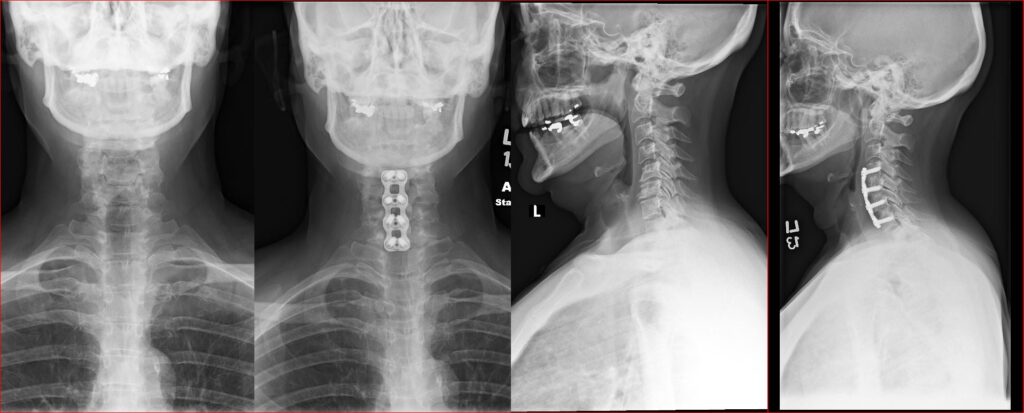

two levels acdf

ACDF C4 7 1024x413